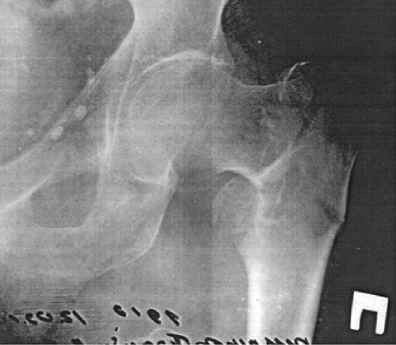

чрезвертельный перелом бедра |

Уважаемые врачи! Извините за сумбурность описания и помогите, пожалуйста разобраться, в каком направлении двигаться. Пожилой человек, 87 лет, закрытый оскольчатый чрезвертельный перелом со смещением.Местонахождение - Алма-Ата.Лежит дома, нога зафиксирована,прошел месяц, самочувствие удовлетворительное, сам пересаживается на каталку.Мы консультировались в ЦИТО - предложен остеосинтез(нужен контрольный снимок).В Алма-Ате-один профессор по снимку сказал -консервативное, другой - эндопротезирование (контрольный снимок не нужен, и так все ясно).Вроде бы эндопротезирование самый быстрый способ, но, судя по информации в сети, зачем он нужен при ЧРЕЗВертельном переломе?Больной - сохранный, из сложностей только гипертоническая болезнь.Что все-таки делать, потому что выехать в Алма-Ату для организации операции смогу только на 20 дней. А там даже доставка на контрольный снимок в отличие от Москвы - большая проблема, не говоря об остальном.

При таком переломе оптимально было сделать остеосинтез в ближайшие дни. Если не сделали, то с большой долей вероятности срастется, но криво, с заметным укорочением.

Что значит "нога зафиксирована", если "сам пересаживается на каталку"? Если пациент пересаживается,нога не зафиксирована, и отломки сместились. Для сращения с правильной длиной и осью нужно продержать паациента на вытяжении с отведенной ногой недель 6.